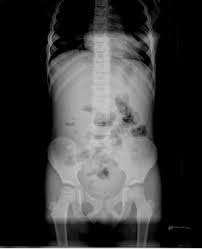

- un scanner

- une radiographie de l’abdomen.